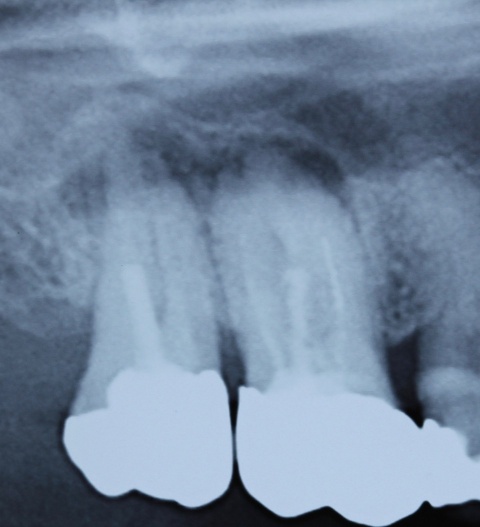

Im nächsten Fall stellte sich ein Patient mit reizunabhängigen Beschwerden und Perkussionsempflindlichkeit an Zahn 17 vor. Begleitend lag eine Lockerung Grad I bis II vor. Das daraufhin angefertigte Röntgenbild (Abb. 5) zeigt eine insuffiziente Wurzelfüllung, nebst Wurzelstift und einer umfangreichen apikalen Osteolyse. Darüber hinaus scheint Zahn 16 ebenfalls apikal beherdet zu sein und im Bereich der mesialen Wurzel besteht der Verdacht eines frakturierten Wurzelkanalinstrumentes.

Nach ausführlicher Aufklärung der vorhandenen Therapiealternativen entschied sich der Patient für die Revisionsbehandlung. Diagnostisch wichtig war in diesem Fall die Bestimmung des inserierten Wurzelstiftes. Röntgenologisch unterscheiden sich Glasfaser- und Metallstifte aufgrund der physikalischen Eigenschaften des Materials deutlich, sodass es sich hier zweifelsfrei um einen Metallstift handelte. Durch das röntgenologisch sichtbare Gewinde ließ sich die Art des Stiftes bestimmen. So war nach Entfernen der Krone das vorsichtige Freischleifen des Stiftkopfes (Abb. 6) wichtig, um den Stift mit einem speziellen Schlüssel ausdrehen zu können (Abb. 7).